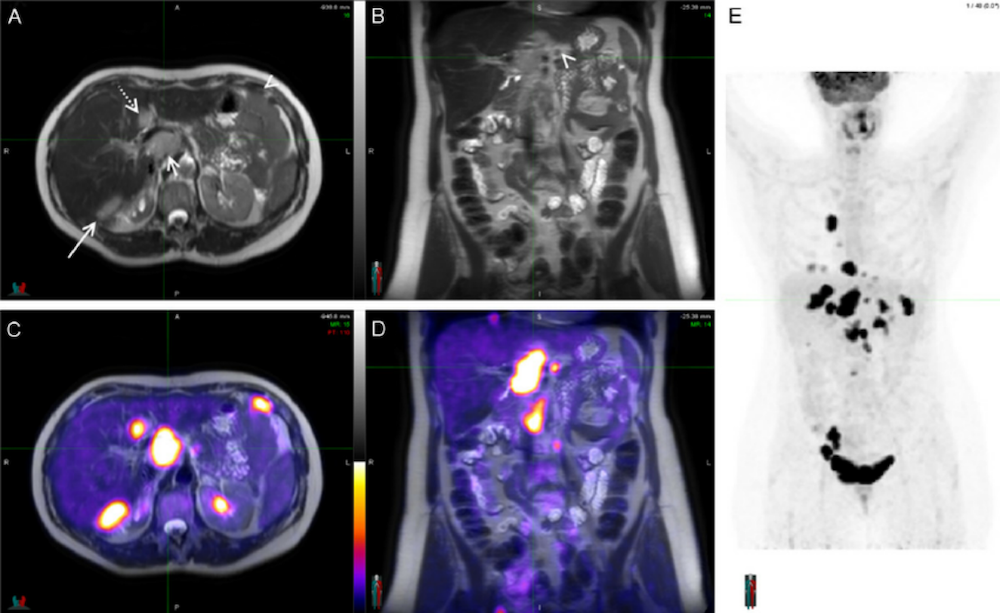

图4:多发性骨髓瘤的18F-FDG PET/MRI图像

图6:胶质瘤的18F-FDG PET/MRI图像,PET/MRI比PET/CT显示病灶定位更加精确